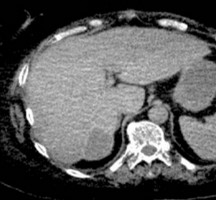

КТ диагностика тубоовариального абсцесса: Подходы и изображения

Раздел: Объективный взгляд